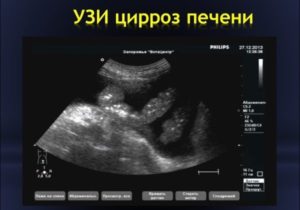

Специфическим симптомокомплексом описывается поздняя стадия цирроза печени, которая встречается при хроническом гепатите С. К нему относятся следующее эхопризнаки:

- уменьшение размеров правой доли органа с увеличения хвостатой;

- неровный и бугристый контур печени;

- выраженная гетерогенность ее структуры, обусловленная чередованием участков повышенной, средней и сниженной эхогенности;

- диффузная гиперэхогенность паренхимы;

- деформации сосудистого рисунка различной степени;

- признаки портальной гипертензии (спленомегалия, увеличение диаметра воротной и селезеночной вен, портосистемные шунты – реканализированная пупочная вена в круглой связке печени, спленоренальные шунты, асцит).

При диагностике цирроза печени наблюдается следующая картина:

- Орган увеличен.

- Край его неровный с постепенным уменьшением и деформированием правой доли.

- Появление спленомегалии.

- Различие картины в зависимости от стадии (острой и хронической).

- При любом течении гепатита наблюдается равномерное увеличение печени.

- Контуры: при остром – ровные, при хроническом могут быть и бугристыми.

- Эхогенность паренхимы: понижена или нормальная при реактивном течении, неизмененная или умеренно повышенная при хронической.

- Нарушение печеночных вен: суженые при острой форме или уплотнения стенок и постепенное сужение при хронической. Эхоструктура: в первом случае гомогенная, во втором – негомогенная.

- Состояние веток воротной вены: «подчеркнутая» гиперэхогенность стенок «звездное небо» и нормальная или расширенная структура.

- Изменения вне печени: для острого гепатита отсутствуют, для хронического – спленомегалия.